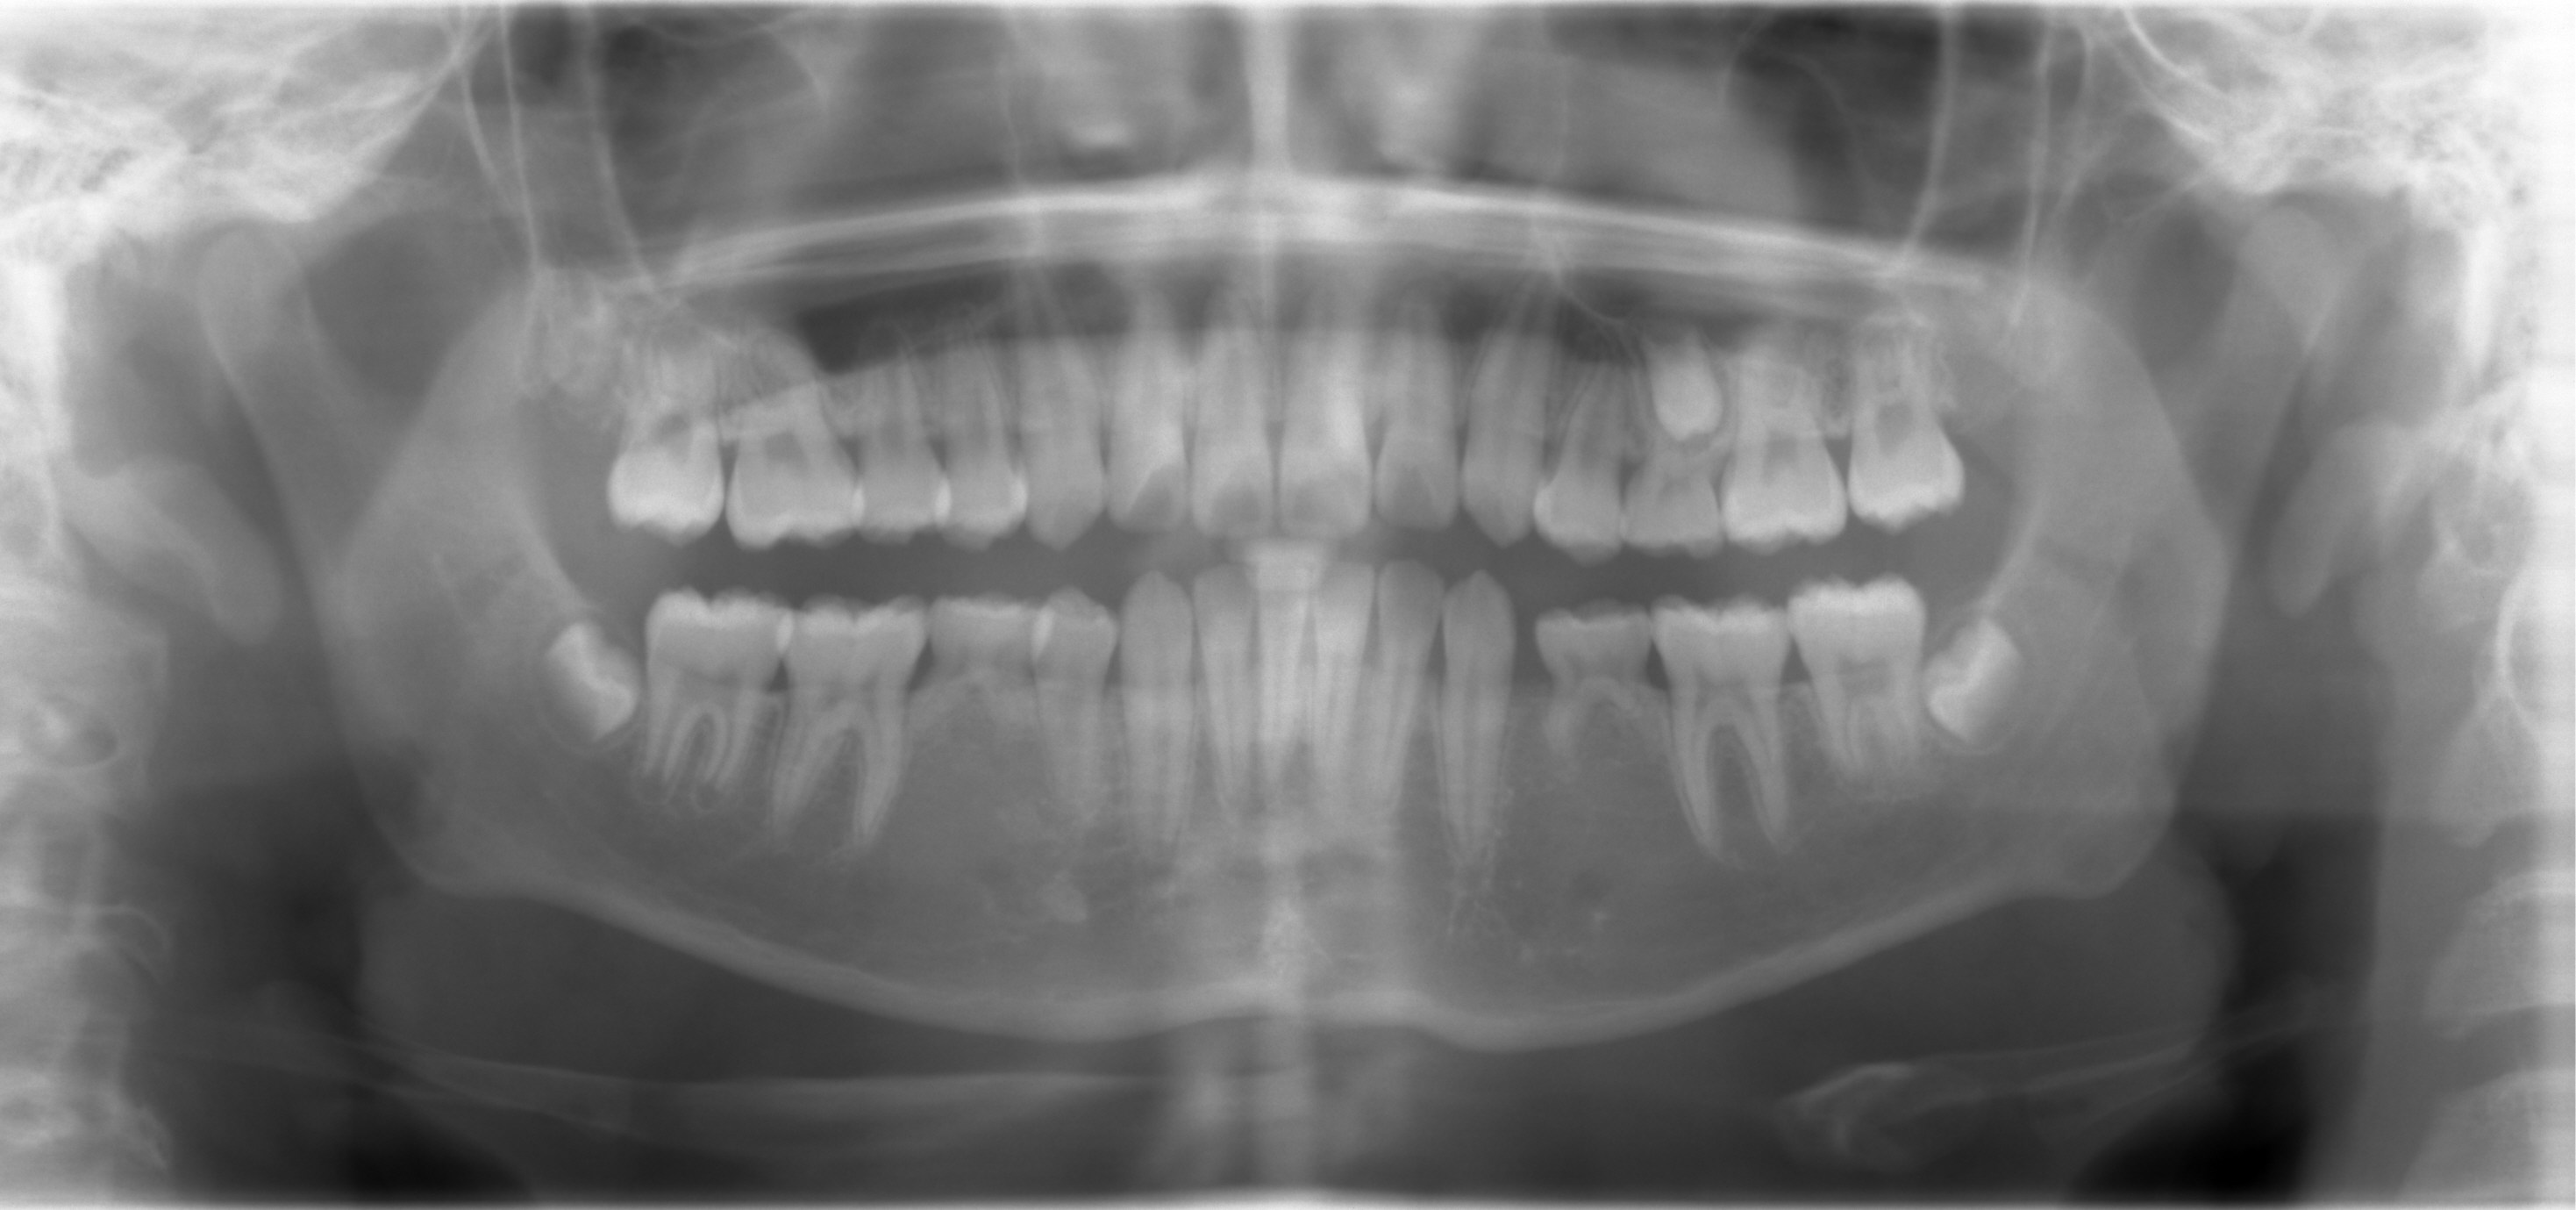

A 13-year-old man returns to clinic 2.5 years after the last one (Fig.1).  UL E is extracted with difficulty.  It appears to be ankylosed.  He returns for follow up today nearly 2 months post extraction.  The socket has healed. UL5 (microdontia) seemingly needs to be extruded orthodonti-cally.  Is it worthy in doing so?  His father having 11 implants (due to trauma and caries instead of congenital nature) is ready for an extra implant if UL5 turns out to be non-salvageable.  Can we extract LR5, mesialize LR6,7 using a mini-implant and let LR8 self mesialize?

Return to Ortho Cases Final X-ray